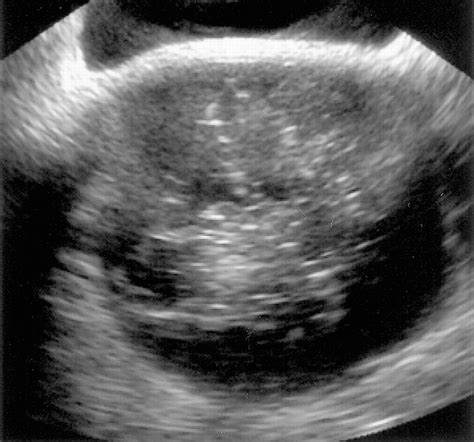

When doctors request scans, they are looking for specific visual identifiers. Imaging techniques such as CT scans, MRIs, and ultrasounds are standard. In these images, a teratoma often appears as a complex mass with both cystic (fluid-filled) and solid components. The presence of fat, calcifications (which look like bone or teeth on an X-ray), and soft tissue elements are hallmark signs that radiologists use to identify the growth.

While looking for Teratoma Cancer Pictures online, patients may see varying representations, but it is important to note that internal clinical imaging (like an MRI) looks significantly different from external surgical photography. Radiology provides the map for surgical intervention, helping surgeons understand the proximity of the tumor to vital organs.